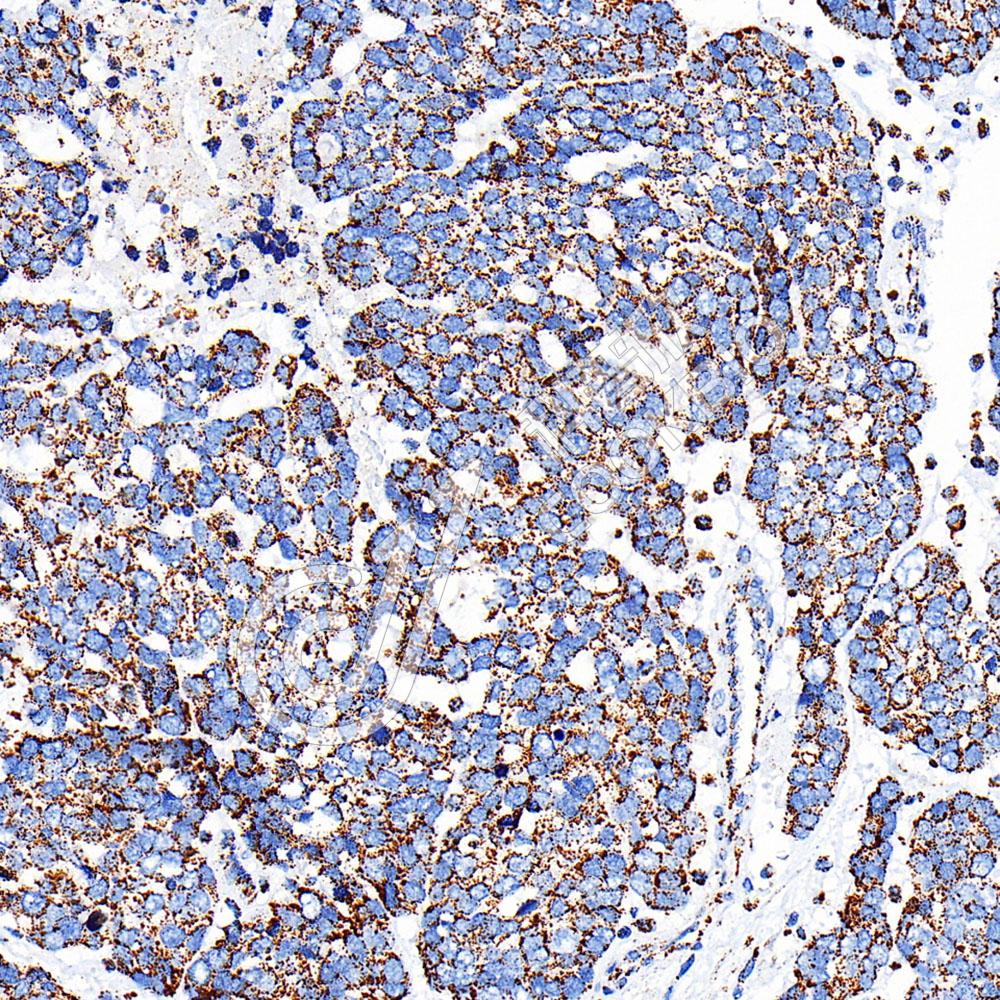

IHC检测TFAM蛋白(货号 K5450252).

样品: 人结肠癌, 4%多聚甲醛 (货号KSG1101) 固定12-24小时.

抗原修复: Tris-EDTA抗原修复液(pH 9.0) (KSG1203), 100℃, 25分钟.

—抗: 1: 800稀释, 4℃ 孵育过夜.

二抗: S-vision免疫组化多聚二抗(山羊抗兔),即用型 (货号KB3906), 室温孵育20分钟.

样品: 人食管癌, 4%多聚甲醛 (货号KSG1101) 固定12-24小时.